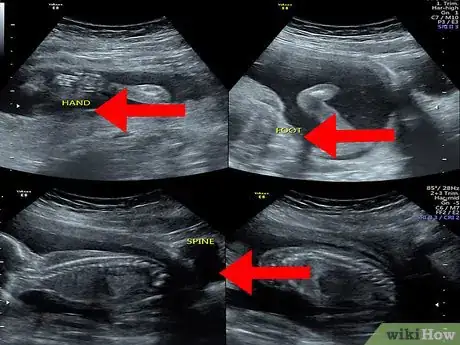

2Spot the baby. Your baby will also look grey or whitish and will be located within the amniotic fluid (the dark area inside of the womb). Look at the area within your amniotic fluid to try to make out the outline and features of your baby.

- The details that you see in the image will depend on the stage of your pregnancy. For example, at eight weeks, the fetus will look something like a gummy bear or a baked bean; at 12 weeks, you may only be able to identify the head of your baby; while at 20 weeks, you may be able to see the spine, eyes, feet, and heart.[8]

3Determine your baby’s sex. At around 18 to 20 weeks, you will have an ultrasound to check your baby’s development, identify any problems, and possibly even identify the sex]] of your baby. It’s important to remember that it is not always possible to determine the sex of your baby at this stage and you won’t know for sure until your baby is born.[9]

- To determine the sex of your baby, the ultrasound technician or obstetrician will look for a penis or three lines that represent the labia. Keep in mind that this method of determining the sex of your baby is not 100% accurate. A visual effect may create or obscure the image of a penis on an ultrasound.